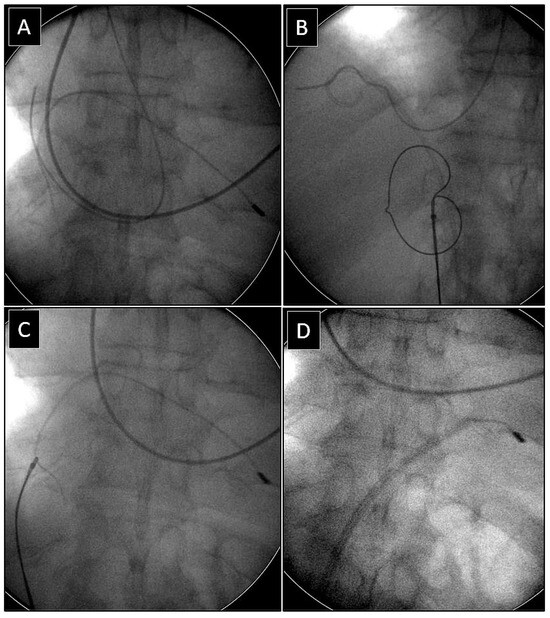

Extraction of Leads with Migrated Proximal Ends into the Cardiovascular Space

| Methods of removing fractured migrant leads | |||||

| Superior approach | 6 (15.39) | 3 (23.08) p = 0.832 | 3 (23.08) p = 0.832 | 5 (71.43) p = 0.007 | 17 (23.61) |

| Combined approach | 3 (7.69) | 3 (23.08) p = 0.316 | 1 (7.67) p = 0.548 | 1 (14.29) p = 0.874 | 8 (11.11) |

| Femoral approach | 29 (74.36) | 7 (53.85) p = 0.298 | 8 (61.54) p = 0.596 | 1 (14.29) p = 0.001 | 45 (62.50) |

| Lasso/basket in CS sheath and a polypropylene or rotational sheath over them (dilatation) | 13 (76.47) | Lasso/basket in CS sheath and a polypropylene rotational sheath over them—superior approach (dilatation) | 8 (100.0) |

| Loop (pulling, end release) | 6 (35.29) | Loop femoral approach | 6 (75.00) |

| Pig-tail + winding and shifting superior approach (end release) | 3 (17.65) | Pig-tail femoral approach | 1 (12.50) |

| Loop femoral approach (pulling, end release) | 35 (77.78) | Lasso/basket in CS sheath—superior approach (pulling only) | 1 (1.39) |

| Pig-tail + winding and shifting femoral (end release) | 7 (15.56) | Lasso/basket only—superior approach (pulling only) | 3 (4.17) |